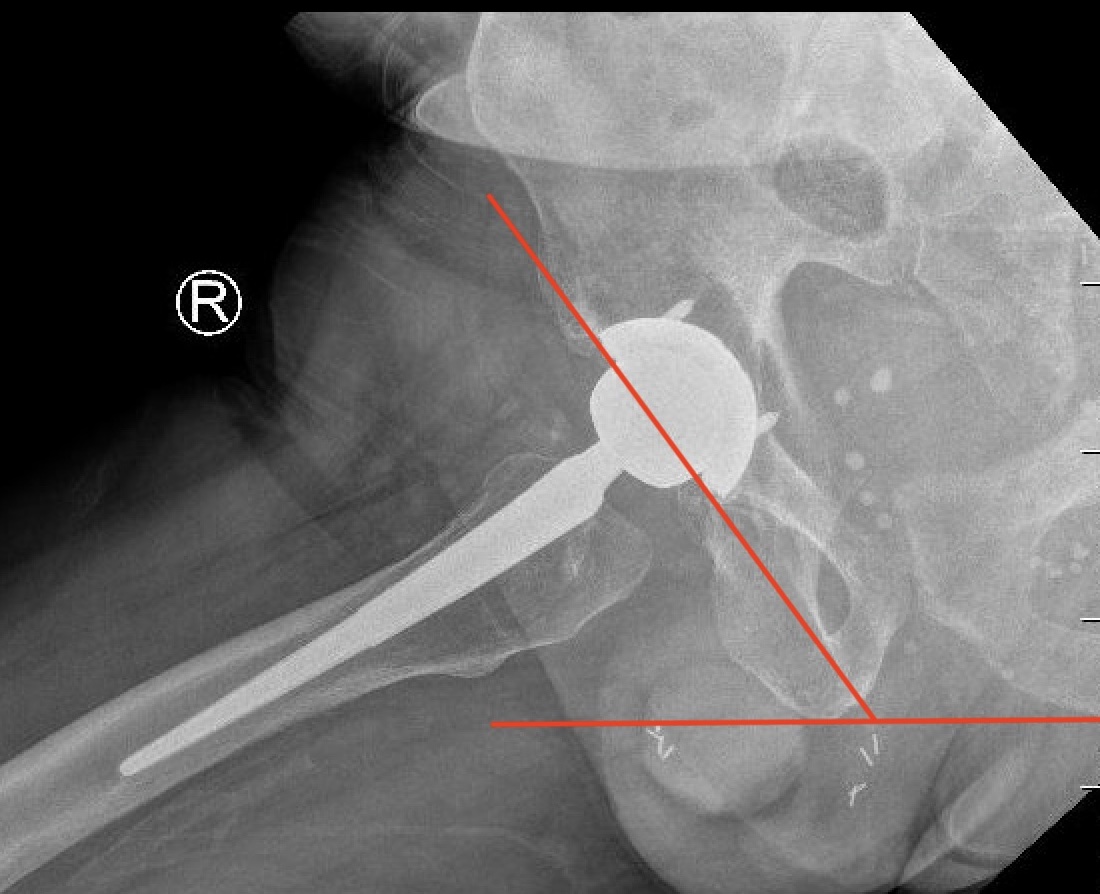

3. Femoral Version

CT scan

- line prosthesis neck

- line posterior femoral condyles